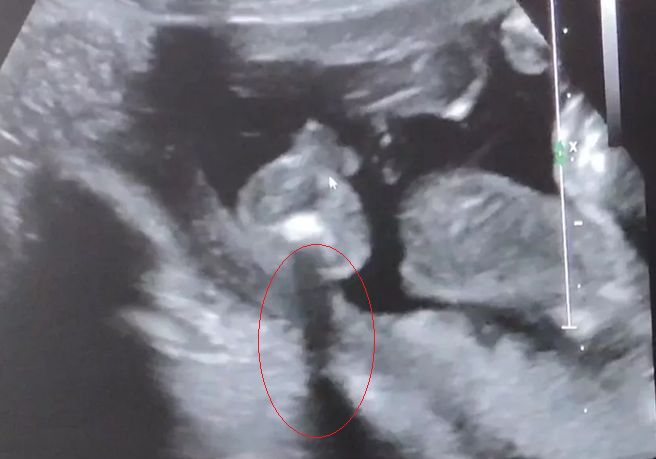

Пришли к УЗИсту узнать пол до скрининга, который сказал, что у меня замершая на 90 проц🤣УЗИст может узнал меня, сказал бесплатно скажет. А мы теперь ему до конца не доверяем. Мышкой показывает мошонку, а мы не совсем понимаем, так как смотрели минуту🤣 как будто справа ноги согнутые и булки понятно

Похоже на мальчика, да. За точность не отвечаю 🤭 Там же внизу попа, указатель мышки на мошонке?

А там мошонка и ещё что-то 🤭